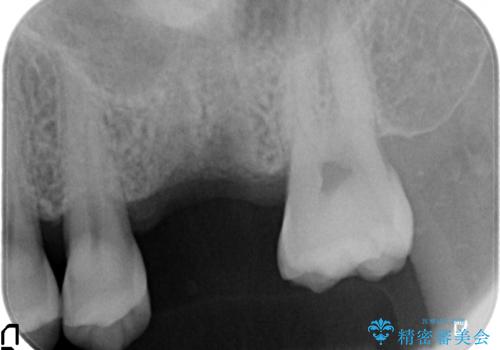

奥歯の欠損 インプラントによる咬合機能回復

- 奥歯を失い噛めないことの治療を希望され来院されました。

臨在する歯が虫歯もなく健全であるため、ブリッジではなくインプラントを用いた機能回復を計画します。